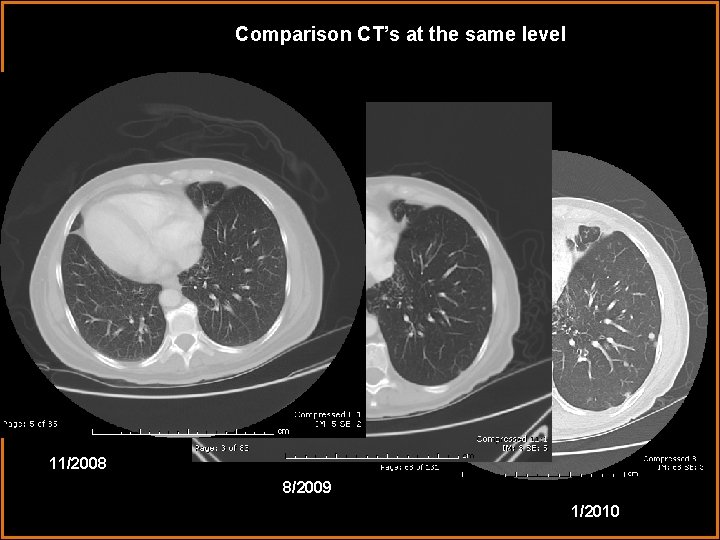

Comparison CT’s at the same level 11/2008 8/2009 1/2010

Discussion Additional findings of the CT included new spiculated nodules likely representing metastatic pancreatic cancer. The patient had a Whipple procedure previously for pancreatic cancer and had subsequently developed pneumobilia, which can be seen status post choledochojejunostomy.

Diagnosis Kartagener syndrome with metastatic pancreatic carcinoma to the lungs status post Whipple procedure with subsequent pneumobilia.